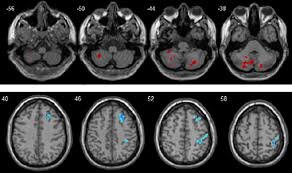

نمونههای MRI واقعی را دیده یاد گرفته الگوهای غیرطبیعی را تشخیص دهد و میتواند نشانههایی مثل: سکته، تومور، خونریزی مغزی، التهاب و آسیبهای بافتی را در تصاویر MRI شناسایی کند. این تحلیل نهفقط سریعتر، بلکه در بسیاری موارد دقیقتر از چشم انسان عمل میکند.

بهاینترتیب بسیاری از بیماریهای مغزی هر لحظه تاخیر در تشخیص میتواند پیامدهای جبرانناپذیر داشته باشد. این فناوری همان «تصمیم سریع» را ممکن میکند.